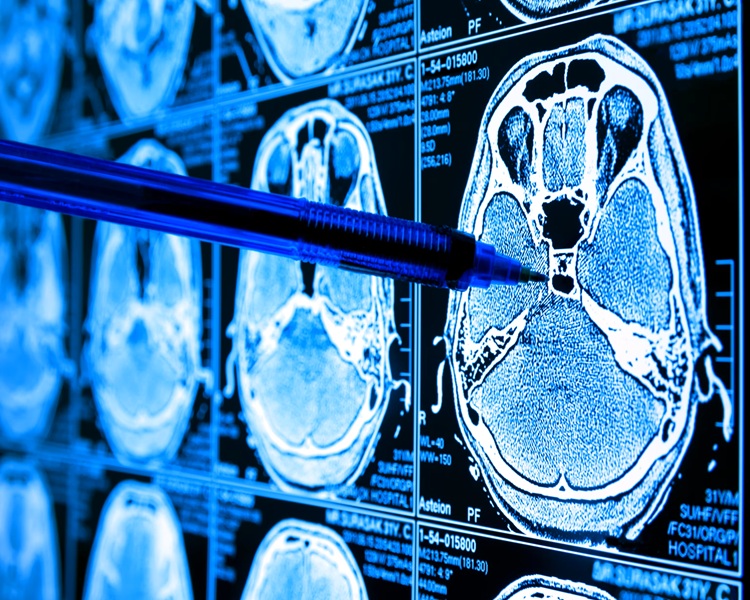

Medical image analysis documentation

Healthcare

Computer vision, segmentation, classification.

Image Processing